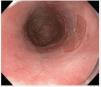

Paciente masculino de 55 años de edad, con enfer-fue sometido a mucosectomía endoscópica con medad por reflujo gastroesofágico. Se realizó pa-técnica de ligadura (figura 2). La endoscopia de nendoscopia, identificándose esófago de Barrett de control mostró tejido esofágico de características segmento largo. La cromoendoscopia digital con normales con signos de cicatrización en el sitio de imagen de banda estrecha (NBI) y magnificación, la mucosectomía (figura 3). El paciente continúa reveló zonas con un patrón tipo Pit IV de la clasi-en protocolo de vigilancia de displasia y con trataficación de Endo1 (figura 1). Las biopsias revelaron miento con inhibidor de bomba de protones. un foco de displasia de alto grado y el paciente

Estudios de imagen:Figura 1. Cromoendoscopia digital con NBI y magnificación en esófago de Barrett, se observa patrón tipo Pit IV.